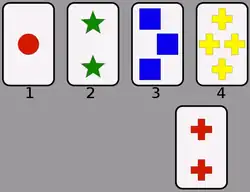

Wisconsin Card Sorting Test (WCST)

The Wisconsin Card Sorting Test (WCST) can be used in conjunction with other tests to speculate to possible dysfunction of the prefrontal cortex, the front-most area of the frontal lobe, that plays an important role in executive functioning. However, since the age of modern medicine and brain imaging, the WCST has been purported to be inaccurate and inconclusive in diagnosing frontal lobe damage.[9]

The WCST test is supposed to specifically measure an individual's competence in abstract reasoning, and the ability to change problem-solving strategies when needed.[10]